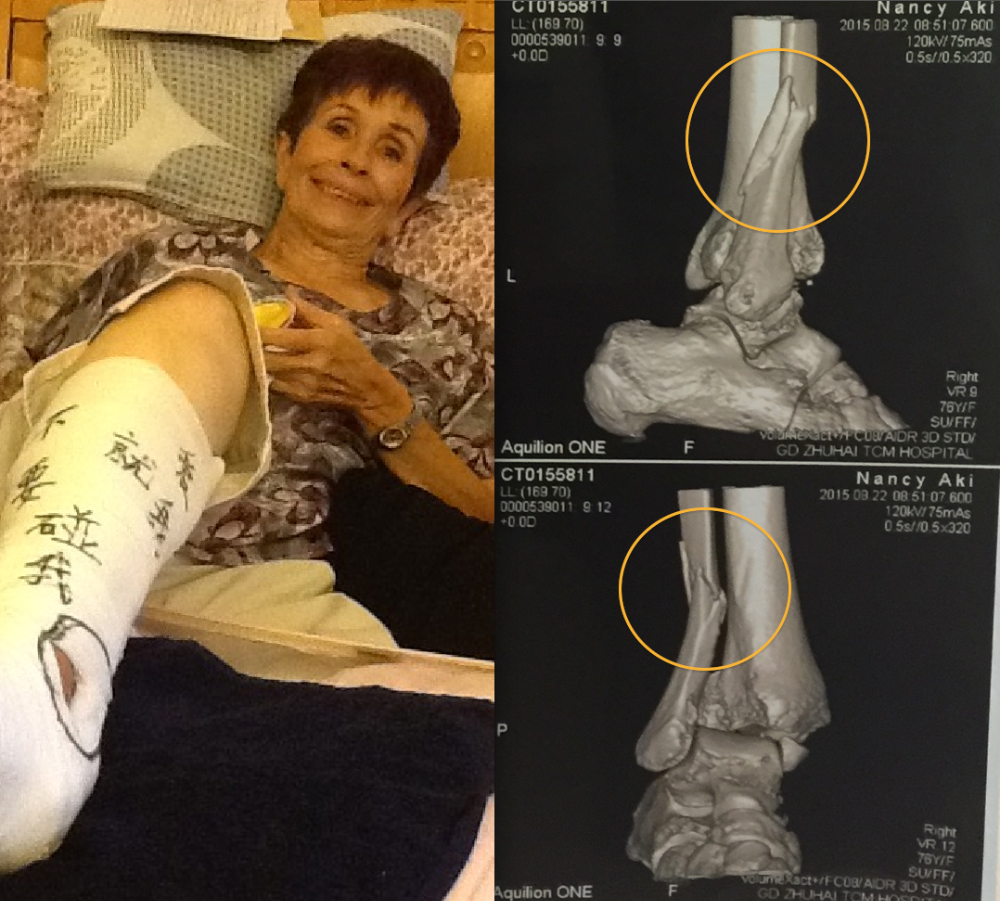

My mom, Nancy (Moore Mallory) Aki, almost 77 years old, needs surgery immediately, or within the next seven days (Sept. 3, 2015), before the broken bones start to set. She severely broke her ankle in 3 different places, is in a lot of pain, and exhausted with barely being able to get up to use the restroom with her crutches. The hole you see in the cast is where the bone is sticking out through the skin.

My mom, Nancy (Moore Mallory) Aki, almost 77 years old, needs surgery immediately, or within the next seven days (Sept. 3, 2015), before the broken bones start to set. She severely broke her ankle in 3 different places, is in a lot of pain, and exhausted with barely being able to get up to use the restroom with her crutches. The hole you see in the cast is where the bone is sticking out through the skin. She currently lives in China alone, and has a small social security income. Hospitals are a bit different in China; most transactions are done in cash. Initially a friend came to her rescue and loaned her the required $500 hospital deposit that took care of most of the costs, tests, etc. She since has returned home from the hospital as the funds have run out even though she needs further treatment.

On Monday she learned that the surgery alone is going to cost $6,000.00. My mom does have Medi-Care in the states, and it would pay 80% of the bill, however, returning to the states for surgery is not an option. The risk of blood clots with a 19 hour flight home is very high, and is in no condition to travel.

How it happened: Thursday, August 20th, she was feeling dizzy and while at the supermarket, went to the restroom, where she blacked out, fell down inside a small squat toilet, and completely turned her ankle sideways. She was taken to the hospital by ambulance.